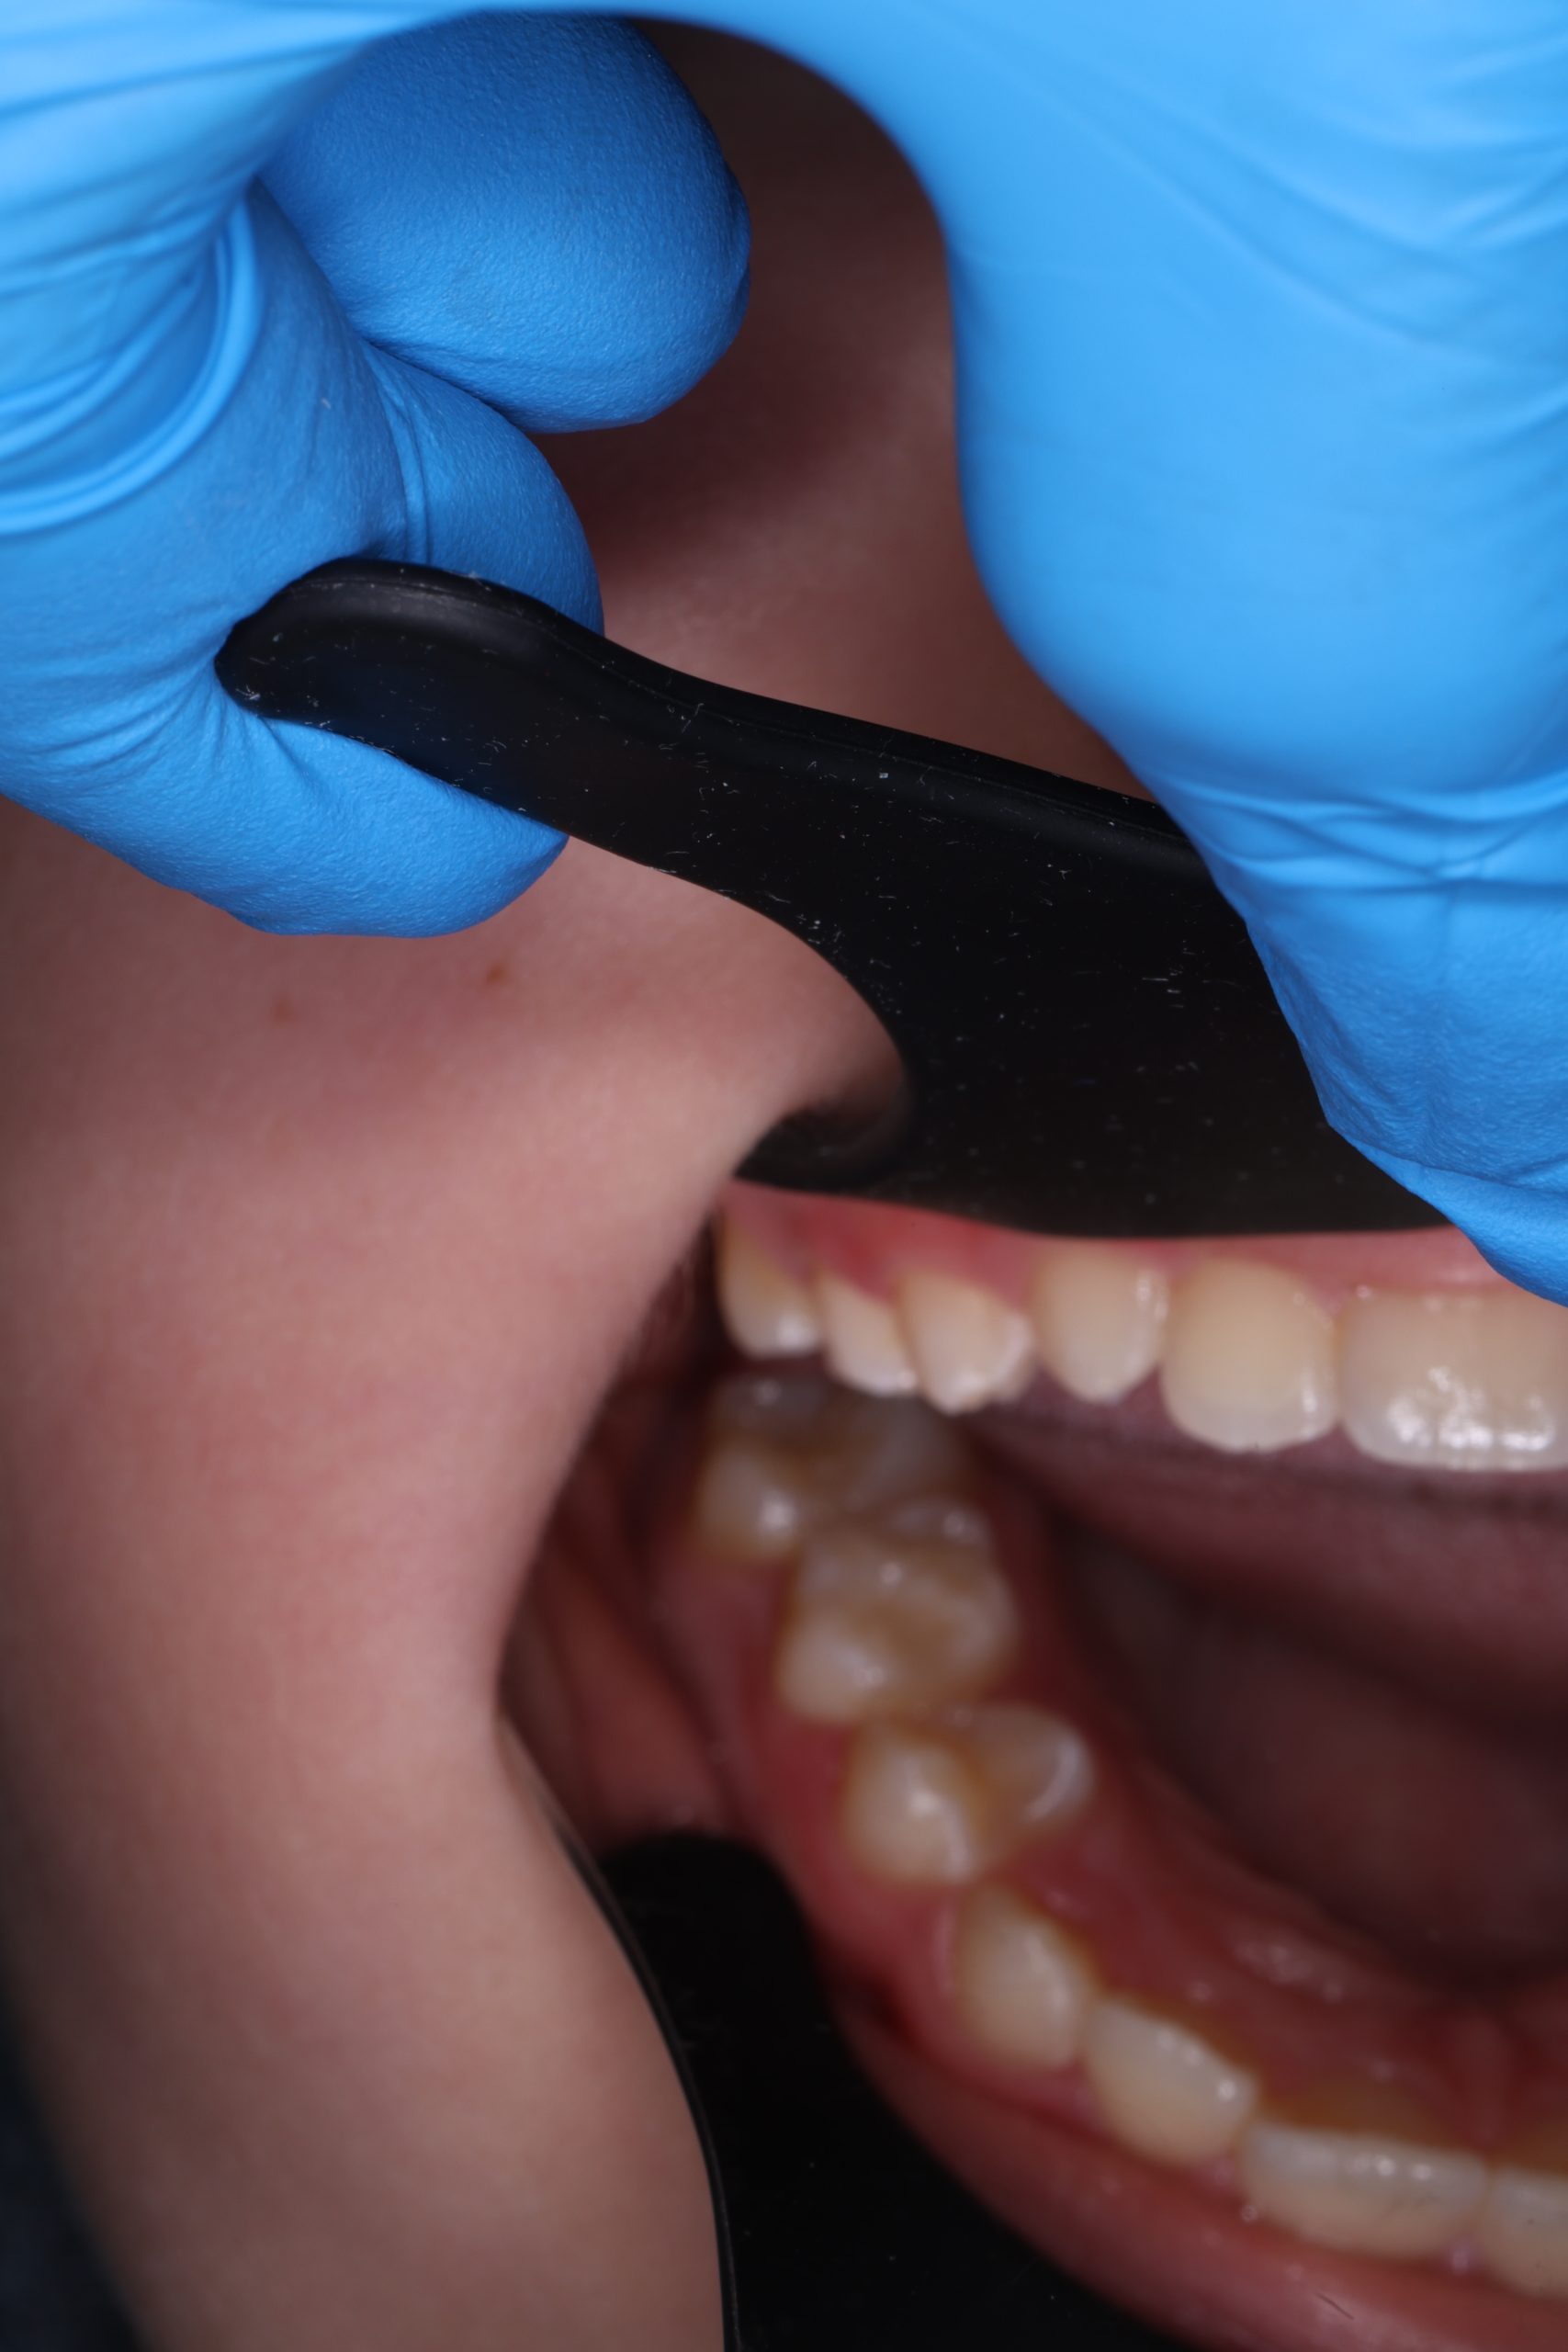

- Detailed Examination

We examine the condition of teeth, gums, and bite. - Plaque Disclosure with Special Indicators